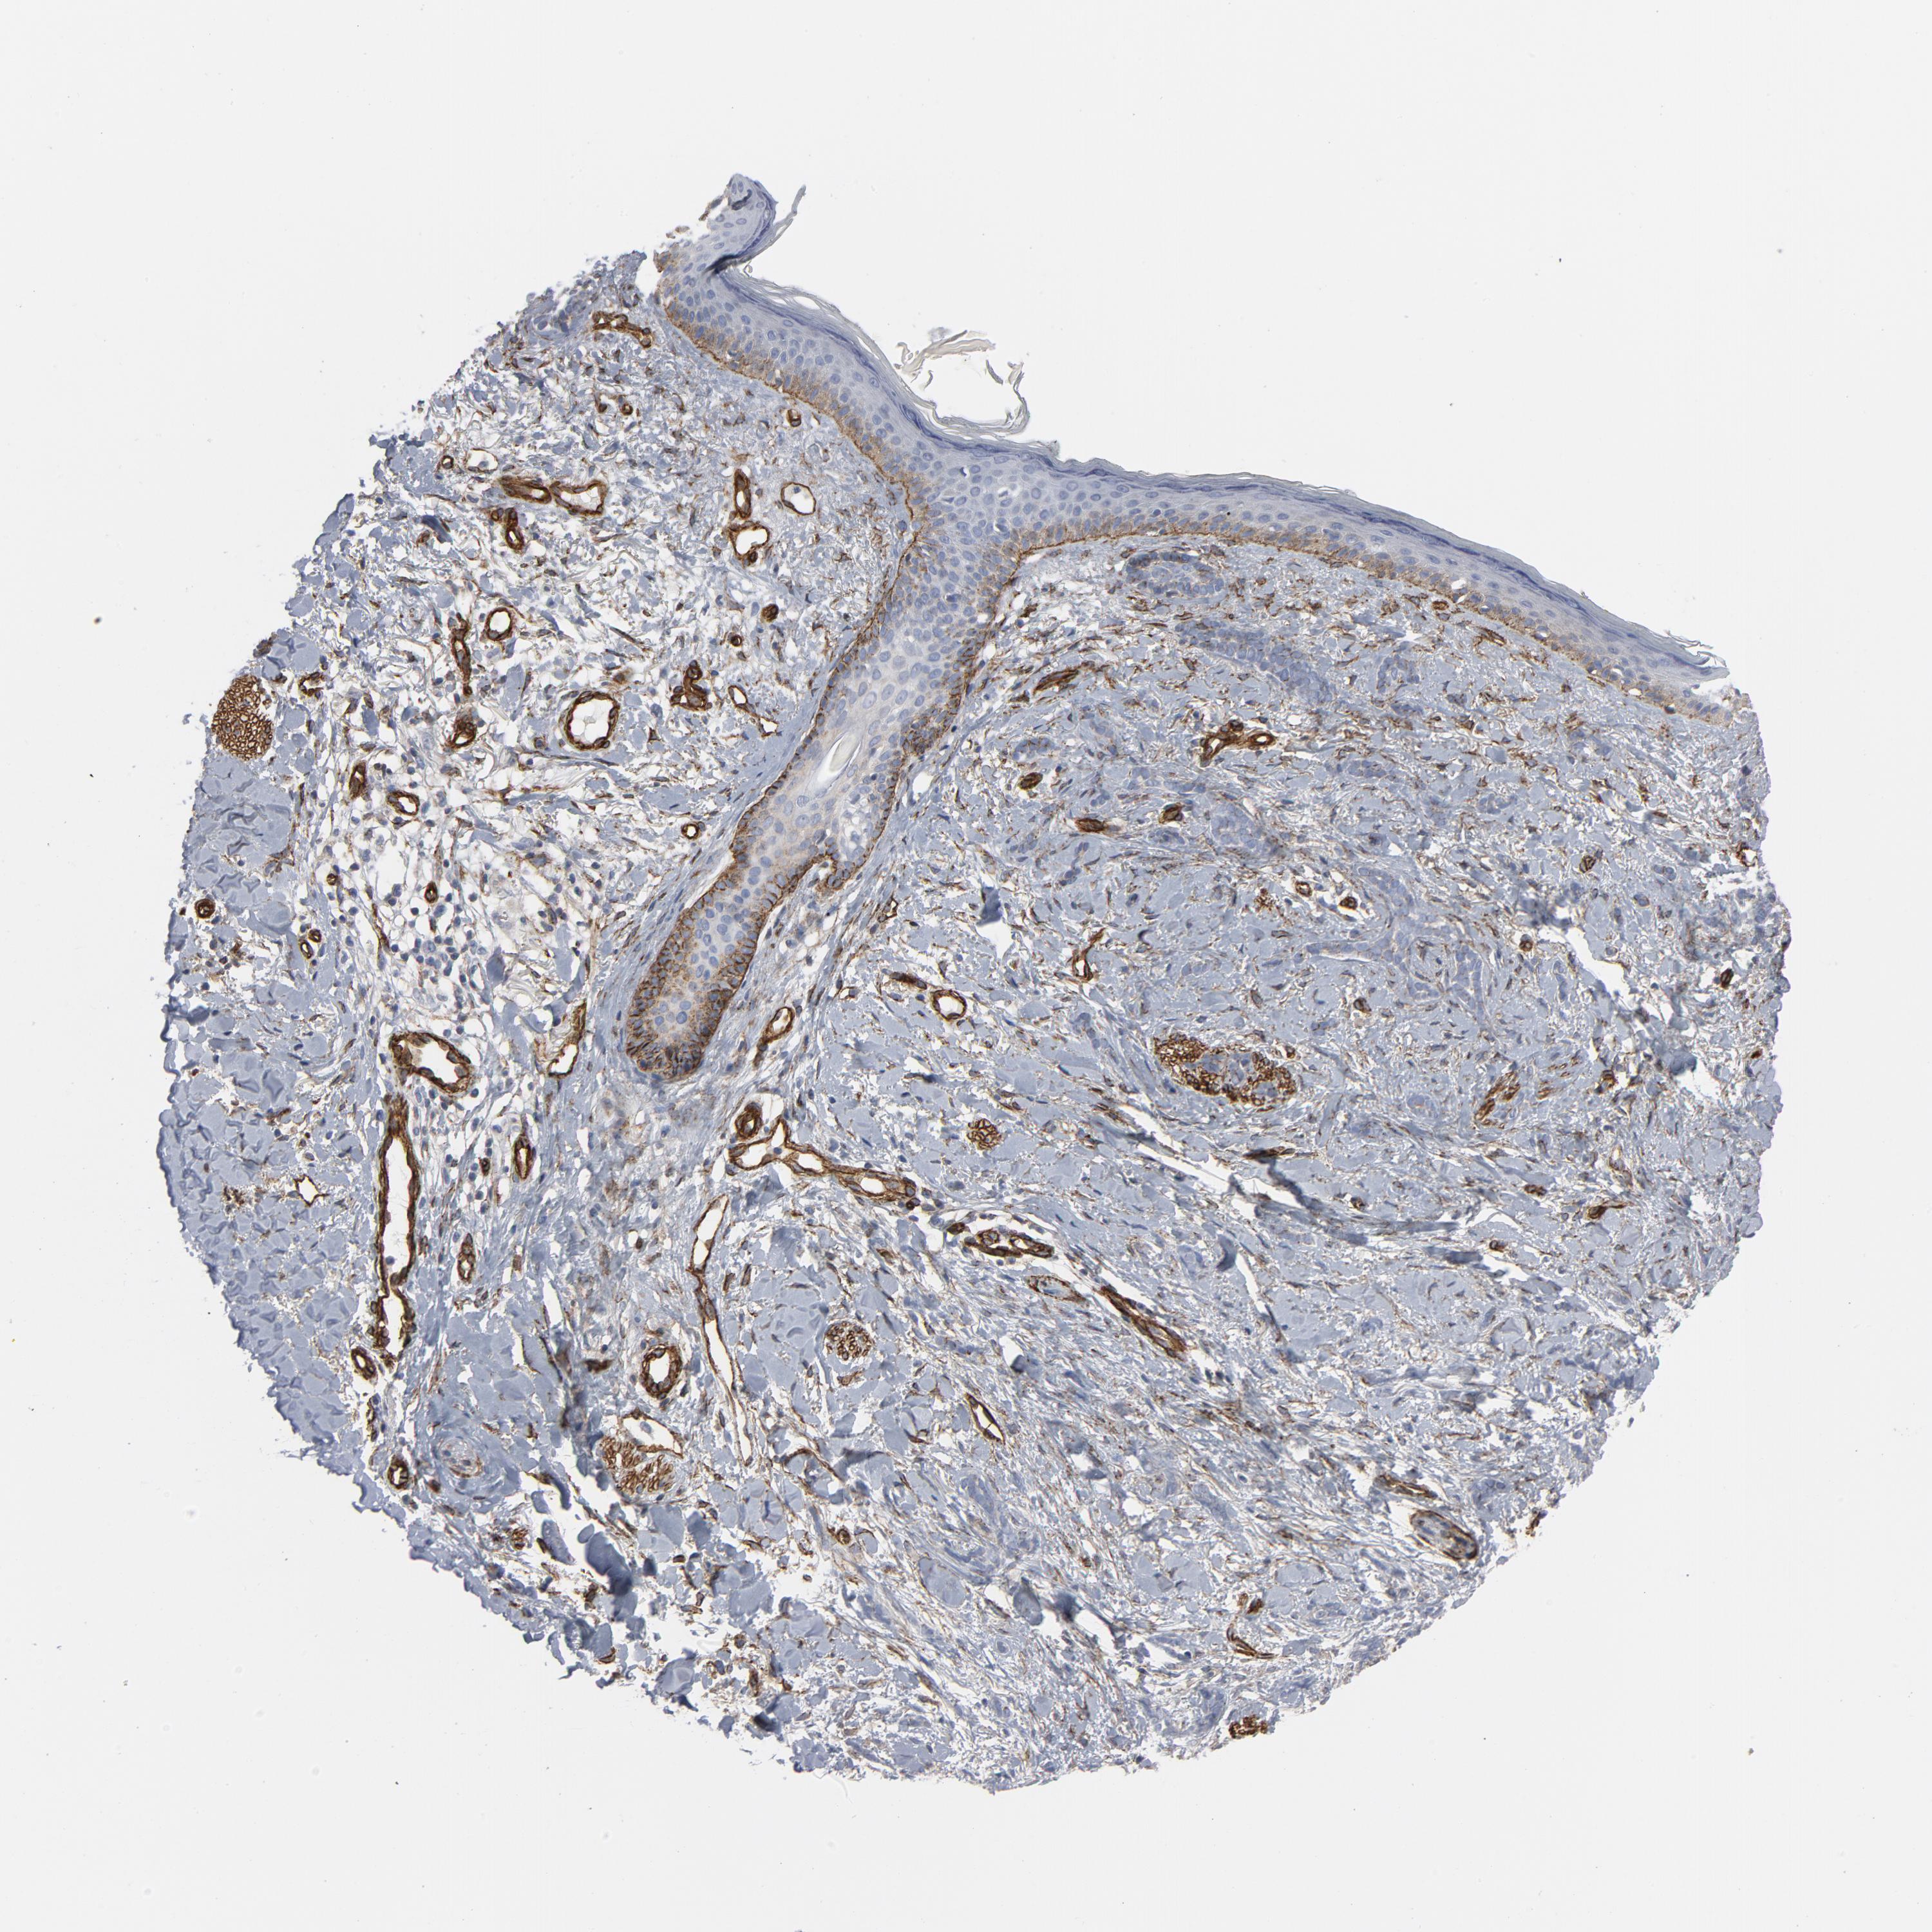

SKIN CANCER - Protein expressioni

A mouse-over function shows sample information and annotation data. Click on an image to view it in a full screen mode. Samples can be filtered based on level of antibody staining by selecting one or several of the following categories: high, medium, low and not detected. The assay and annotation is described here.

Each image is clickable and will lead to virtual microscopy that enables deeper exploration of all samples and also displays staining intensity scores, fraction scores and subcellular localization as well as patient and tissue information for each sample.

Antibody HPA003534

Staining

High

Medium

Low

Not detected

Intensity

Strong

Moderate

Weak

Negative

Quantity

>75%

75%-25%

<25%

None

Location

Nuclear

Cytoplasmic/membranous

Cytoplasmic/membranous,nuclear

Squamous cell carcinoma, NOS

Basal cell carcinoma

Squamous cell carcinoma in situ, NOS

Squamous cell carcinoma, metastatic, NOS

Adnexal tumor, benign